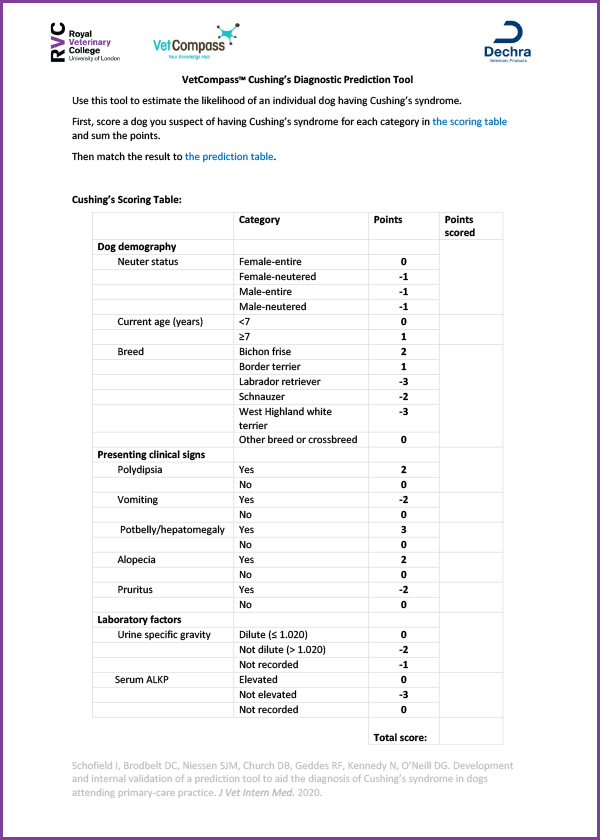

The tool was developed after the application of advanced statistical methods and is made up of 10 ‘predictive’ factors for Cushing’s syndrome. The tool reports the probability of an individual dog having Cushing’s syndrome, based on these factors.

This study was made possible due to access of large volumes of anonymised data through the VetCompassTM programme and funding from Dechra Veterinary Products Ltd. The study included data from hundreds of dogs tested for Cushing’s syndrome across 886 UK veterinary practices and used data on dogs’ demographics, clinical signs at presentation and laboratory results.

The tool is available as a free download: VetCompass™ Cushing’s Diagnostic Prediction Tool (pdf)